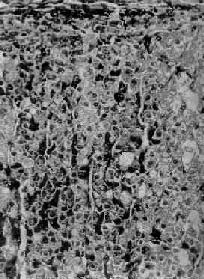

图15-14 肾上腺皮质弥漫增生 图15-13之镜下观,肾上腺皮质束状带弥漫性增厚 2.异位分泌ACTH或CRF肿瘤肾上腺变化与上述同。 3.肾上腺皮质结节性增生(adrenocortical nodular hyperplasia)其原因不明,有的呈家族性。双侧肾上腺明显肥大,重量可超过50g,在弥漫增生的基础上又有许多增生的结节,大小不等,直径从数毫米至2.5cm。镜下,弥漫增生者主为网状带及束状带细胞,而结节内多为束状带细胞,常见多量脂褐素,致结节呈棕褐色。患者血清ACTH水平下降。 4.功能性肾上腺肿瘤 除肿瘤变化外,血清中ACTH减少,致使肾上腺非肿瘤部分萎缩。 5.长期使用糖皮质激素类药物 例如地塞米松(dexamethasone),由于反馈抑制垂体前叶释放ACTH,故血清中ACTH等减少,双侧肾上腺皮质萎缩。 (二)醛固酮增多症 原发性醛固酮增多症(primary aldosteronism)是肾上腺皮质增生的细胞分泌过多的醛固酮所致,引起高血钠症、低血钾症及高血压。本症血清中肾素降低,这是由于钠潴留使血容量增多,抑制了肾素的释放。本病80%是由于功能性肾上腺肿瘤引起,其余为原因不明的两侧肾上腺皮质增生等,这种增生常呈弥漫性,有时也呈结节状,镜下主要为球状带细胞增生,有时也混杂些束状带细胞。 继发性醛固酮增多症是由于各种疾病造成肾素分泌增多所致,肾素可使血浆中的血管紧张素原转变为血管肾张素,后者刺激球状带细胞使醛固酮的分泌增多。